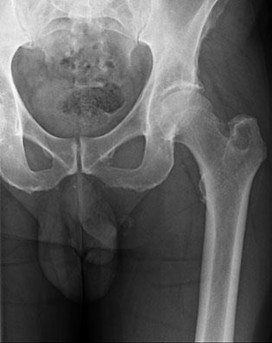

Question 4

A 65-year-old male who underwent a cementless total hip arthroplasty (THA) 15 years ago presents with new-onset thigh pain. Radiographs reveal eccentric positioning of the femoral head within the acetabular shell and large retroacetabular and proximal femoral radiolucencies.

What is the primary biological mediator released by macrophages that directly stimulates osteoclastogenesis and is responsible for the observed bone loss?

Explanation

The radiograph demonstrates particle-induced osteolysis, secondary to polyethylene wear debris. When macrophages phagocytose these particles, they release pro-inflammatory cytokines, most notably TNF-a, IL-1, and IL-6. These cytokines stimulate the RANK/RANKL pathway, activating osteoclasts and leading to significant periprosthetic bone loss. IL-10 and IL-4 are anti-inflammatory cytokines, while IFN-y actually inhibits osteoclastogenesis.